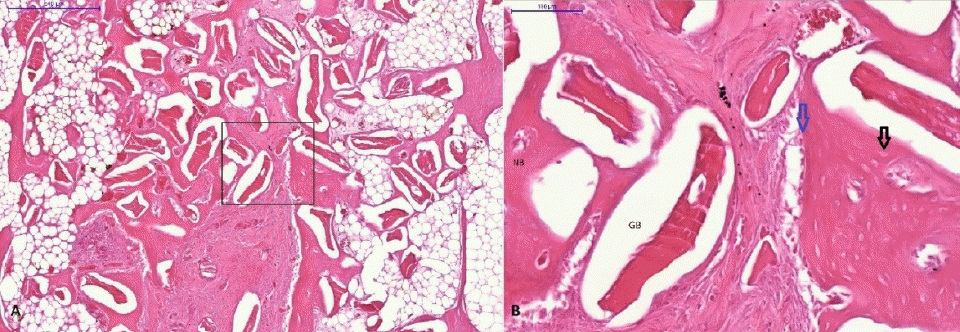

Figure 5.

H&E images of G4 (bovine inserted after extraction) at 4 weeks postoperatively

A: Scale bar is 500 μm, B: An image zoomed in at 5x magnifiaction of the rectangular area in Figure

A (Scale bar is 100 μm) Osteoblastic reaming (blue arrow), osteocyte in the new bone (black arrow),GB: Grafted bone, NB: New bone